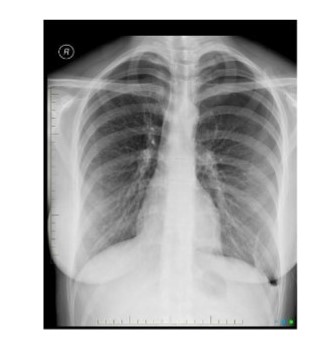

Diagnosis?

knowt flashcard image